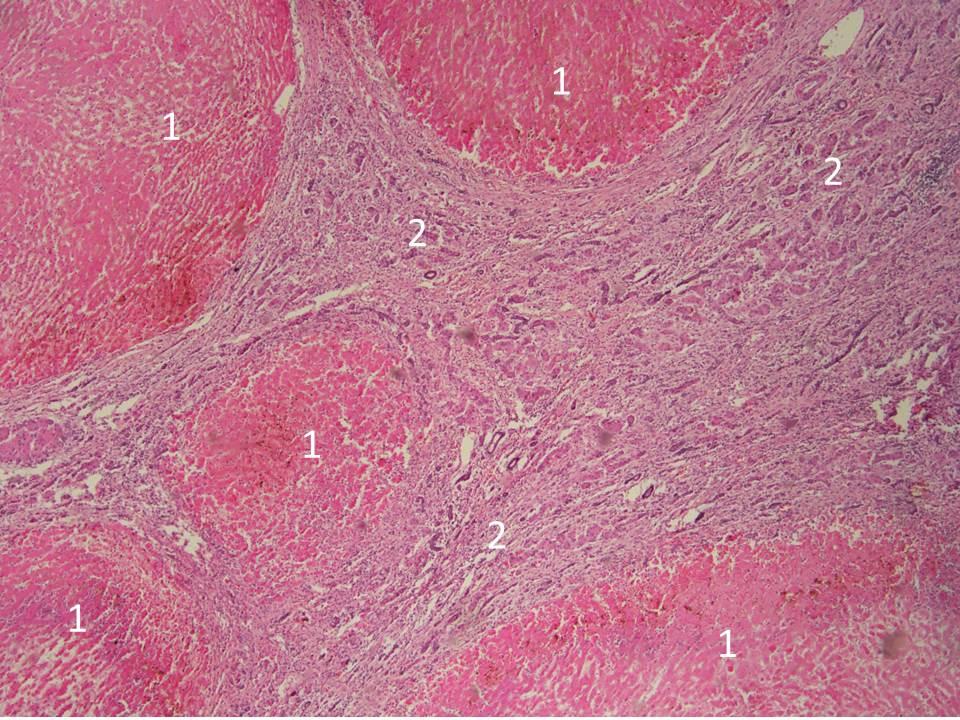

Микропрепараты: Лимфогранулематоз и Нодулярный Склероз